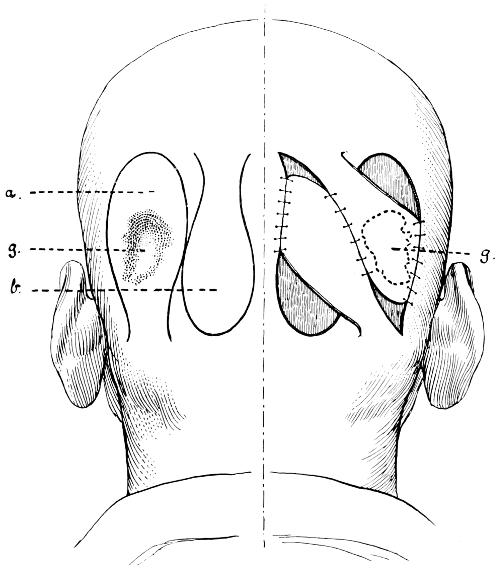

Fig. 1. Cranio-cerebral Topography. 1, The nasion; 2, The inion; 3, The mid-point between nasion and inion; 4, The Rolandic fissure; 5, The superior temporal crest; 6, The inferior temporal crest; 7, The Sylvian point; 8, The anterior horizontal limb of the Sylvian fissure; 9, The vertical limb of the Sylvian fissure; 10, The posterior horizontal limb of the Sylvian fissure; 11, The parietal prominence; 12, The malar tubercle; 13, The lambda; 14, The first temporo-sphenoidal sulcus; 15, The external parieto-occipital sulcus; 16, The lateral sinus; 17, 17, 17, The level of the base of the cerebrum; 18, The external auditory meatus; 19, 19, Reid’s base-line. (Reproduced, by the permission of Mr. H. K. Lewis, from the author’s work on ‘Landmarks and Surface-markings’.)

Larger illustration (top)

Larger illustration (bottom)

[3]

Fig. 2. Cranio-cerebral Topography. 1, 1, Reid’s base-line; 2, 2, A line parallel to the above at the level of the supra-orbital margin; 3, The middle meningeal artery; 4, The anterior branch; 5, 5, 5, The three sites for trephining; 6, The posterior branch; 7, The site for trephining; 8, The point for trephining to reach the descending horn of the lateral ventricle; 9, The lateral sinus; 10, The inion; 11, The mastoid process; 12, Macewen’s suprameatal triangle; 12a, The mastoid antrum; 12b, The facial nerve; 13, The suprameatal and supramastoid crests; 14, 14, The temporal crest; 15, The temporal fossa; 16, The external angular frontal process; 17, The tendo-oculi attachment; 18, The lachrymal groove. (Reproduced, by the permission of Mr. H. K. Lewis, from the author’s work on ‘Landmarks and Surface-markings’.)